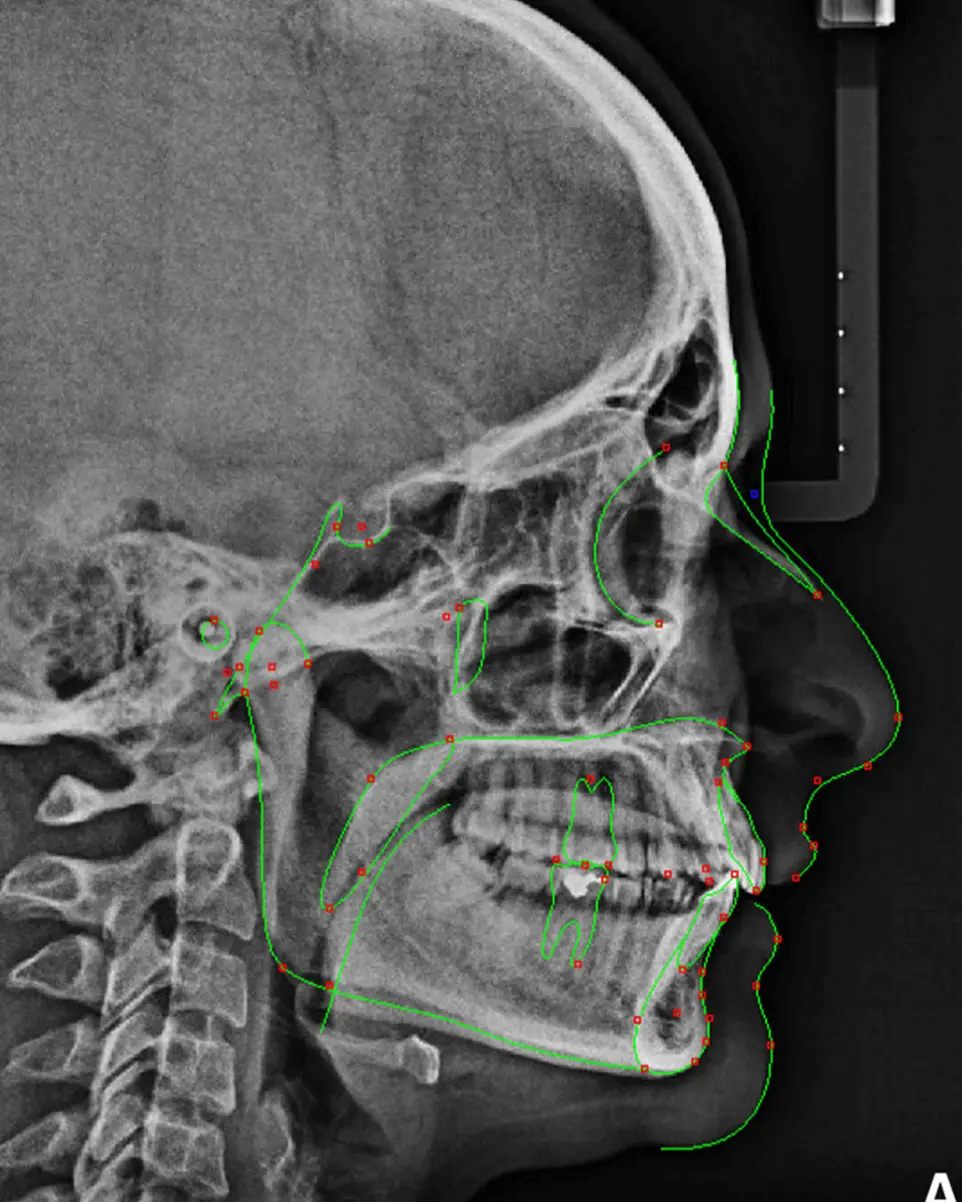

• Lateral de Cráneo: Indispensable para trazos cefalométricos en ortodoncia.

Radiografía Lateral Cráneo